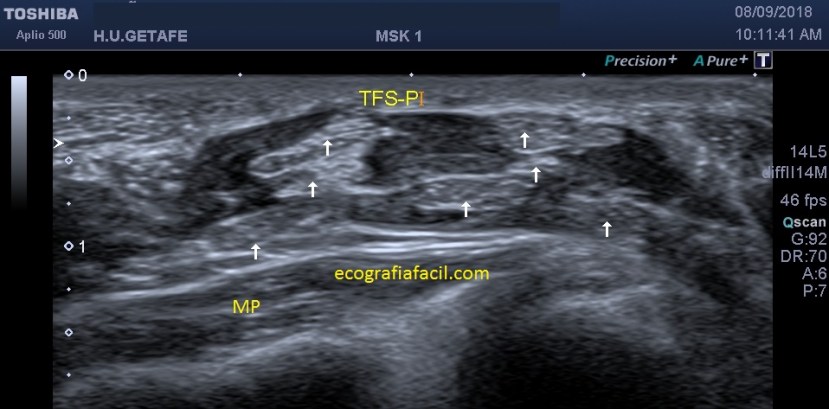

En las siguiente imágenes vemos normalidad de fibras y grosores, con grosores y alteración del patrón normal del tendón…

La imagen superior muestra un corte longitudinal del tendón tendinopático con técnica panorámica desde la inserción hasta el tercio medial de la pierna por la parte posterior, lógicamente.